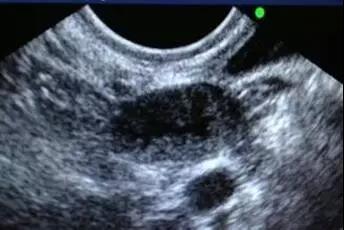

進入IVF周期后,在月經周期第2~3天,需至生殖中心行基礎超聲檢查,通過測量雙側卵巢內竇卵泡的大小及個數,評估本周期卵巢的基礎狀態,以確定促排卵的方案及藥物劑量。如果有優勢卵泡提前出現者,根據的個體情況,制定下一步治療方案。

在啟動促排卵藥物4~5天后,需要再次行超聲監測,觀察雙側卵巢內生長卵泡的發育情況,包括優勢卵泡大小、數目、子宮內膜厚度、及盆腔情況,進行藥物的調整,可能包括:

此后隨著優勢卵泡逐漸增大,卵泡的超聲監測相對更加頻繁,直至卵泡發育成熟,到達HCG扳機標準,一般共約3~5次卵泡監測,注射后36~37小時在陰道超聲進行取卵術。